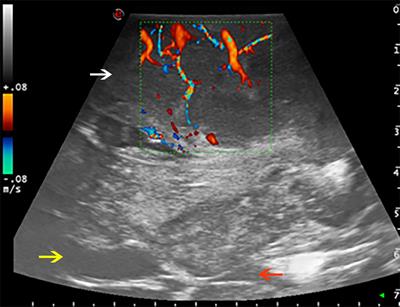

Gynecologic Ultrasound Primer How Not To Miss The Diagnosis